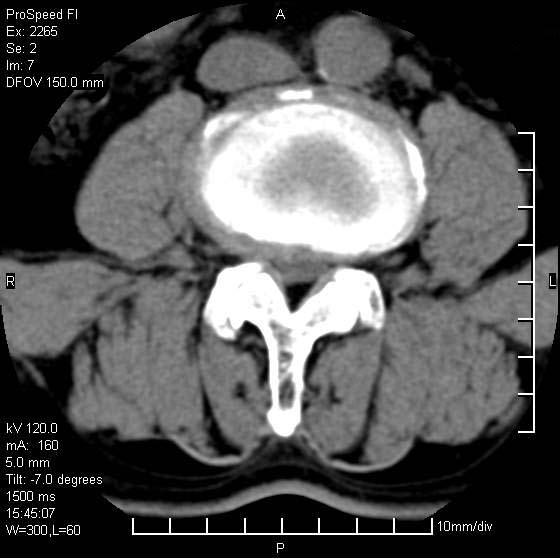

以下是引用qiushi在2007-8-22 17:26:00的发言:[br]没骨窗![br] 1、 l5~s1间盘膨出伴轻度突出(中央型)、变性。[br] 2、l4~5间盘膨出伴突出(右侧远外侧型)。[br] 3、l3~4间盘膨出。[br] 4、腰椎退行性变。[br]

以下是引用随缘的人在2007-8-22 20:56:00的发言:[br]腰椎退行性变:1。l4/5,l5/s1膨出[br] 2。l5/s1间盘退行性变 [br] 3。腰椎骨质增生

以下是引用liaizhi在2007-8-22 22:13:00的发言:[br]1,l4-5锥间盘膨出,2,l5-s1椎间盘膨出并退变(椎间盘呈真空征);3,血管瘤(椎体骨小梁稀疏粗大)?